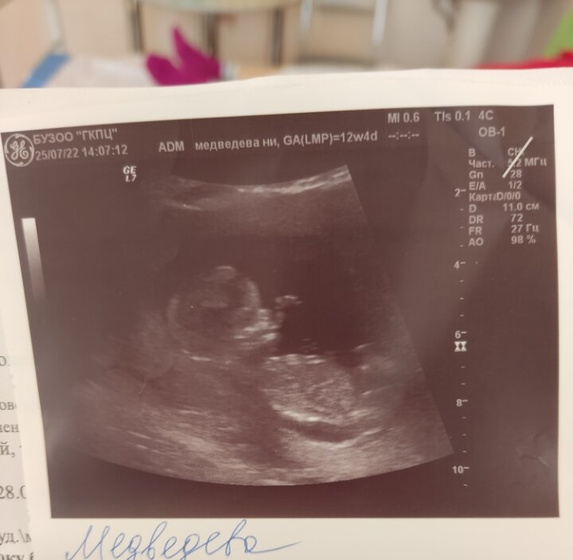

Прошла первый скриниг УЗИ все славо богу хорошо с ребёнком❤ , боже как я переживала и переживаю насчет крови ? Но думаю о хорошем ☺по месячным 12.4 по УЗИ 13.1

Танцевал не давал замерить себя ?

29 января по УЗИ. В обменке писали при постановки на учёт 5 февраля